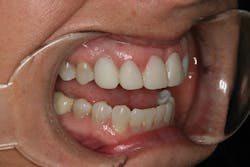

A 32-year-old white female presented for a cosmetic consultation. The patient reported that during her teenage years she had received orthodontic treatment to move her permanent maxillary canines mesially into the spaces that should have been occupied by her congenitally missing lateral incisors. She stated that her dentist, orthodontist, and oral surgeon had decided to place endosseous implants in the canine spaces due to the greater availability of bone in comparison to the bone available in the lateral positions (figure 1). As she grew older, she had become increasingly dissatisfied with the appearance of her smile and was seeking a more updated and esthetic solution (figure 2).

Figure 1